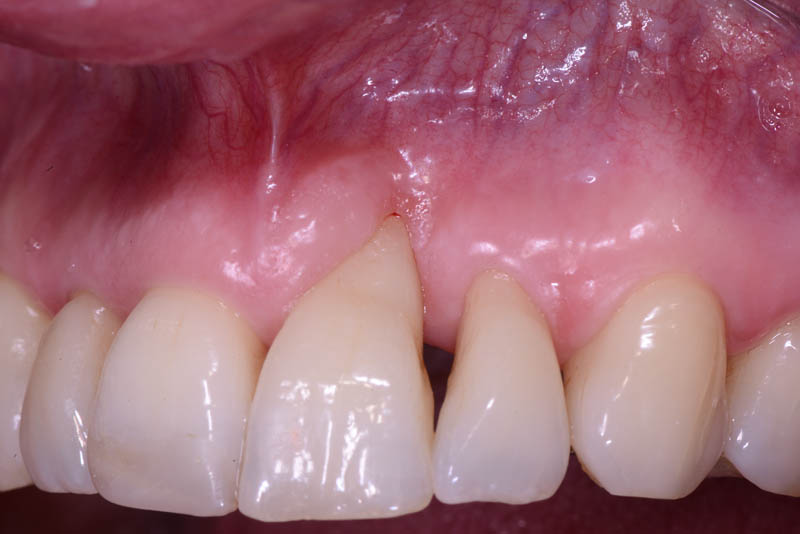

The healing has now reached a 5-year follow-up.

The patient is absolutely delighted with the outcome, but I have repeatedly (and unsuccessfully) encouraged her to undergo a small additional graft to address the minor residual recession on tooth 21.

I even offered to perform the graft free of charge, but she declined.

But then, is it really in the patient’s best interest to undergo another surgical procedure just to fulfill my personal desire for a perfect result?

Even if imperfect, I’m sharing this case.

but it was undoubtedly the best choice for the patient.